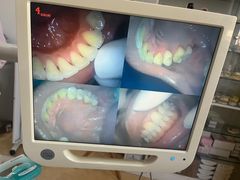

• 赫尔森口腔·牙齿种植修复

• -赫尔森口腔·牙齿种植修复